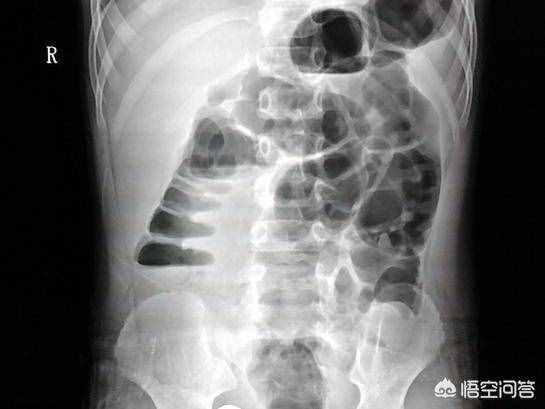

(下图为肠梗阻后气体堆积在肠道中)